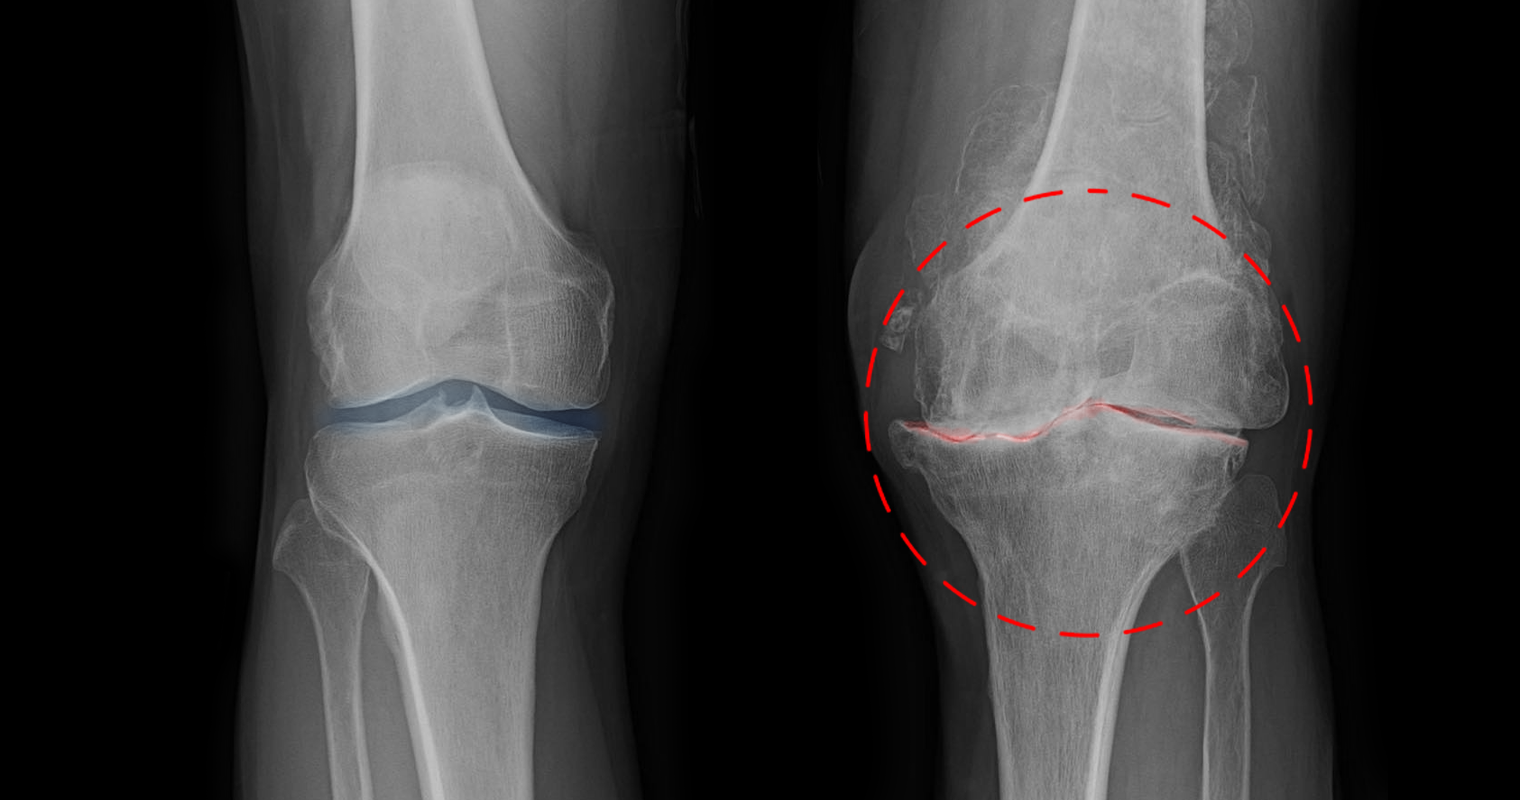

What if I told you that the pain, stiffness, and grinding in your knees aren't actually caused by "worn-out cartilage"?

The knee joints are literally drying out, and your cartilage loses its protective cushion.

The bones start scraping together with every movement: walking, climbing stairs, even just standing up from a chair.

All this friction constantly wears away the cartilage and inflames the joint, which is what causes that swelling, stiffness, and relentless pain.

Left untreated, the cartilage can wear away completely until it's just bone rubbing on bone.